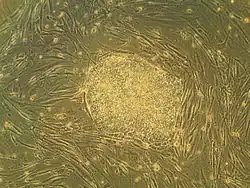

Эмбриональные стволовые клетки человека в клеточной культуре